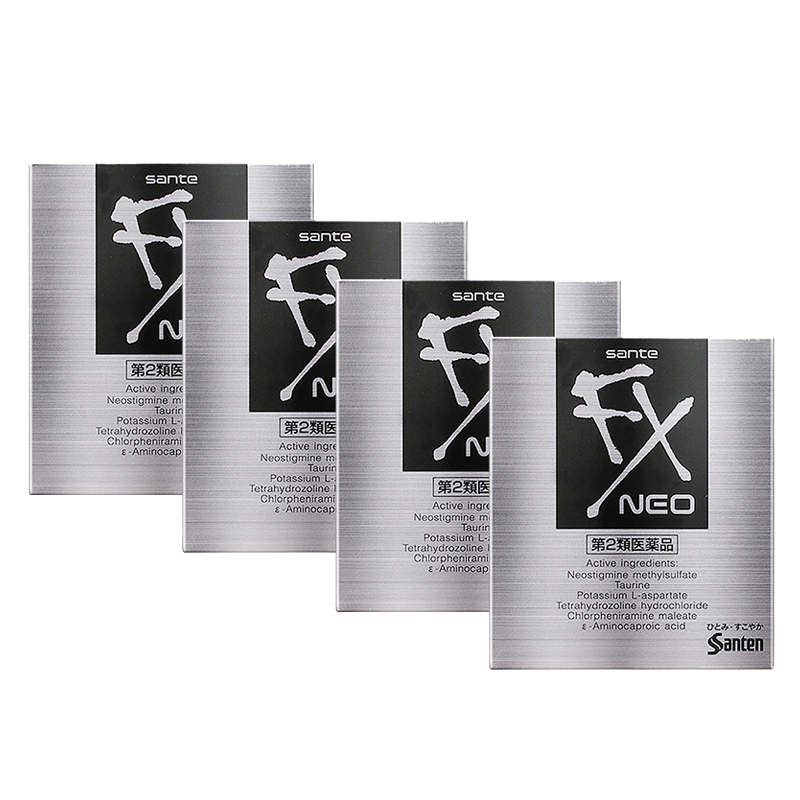

【推荐】美德乐乳头羊脂膏37g纯乳头膏哺乳孕期产妇防皲裂满176.0元减108.0元 【自营】日本参天FX眼药水滴眼液润眼液12ml*4清凉型银瓶眼睛疲劳满240.0元减6.0元

【自营】日本参天FX眼药水滴眼液润眼液12ml*4清凉型银瓶眼睛疲劳满240.0元减6.0元